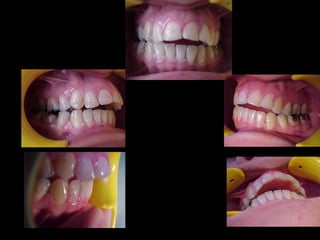

Antes (arriba) Después (derecha)

En términos generales podemos decir que la

paciente tiene una cara armónica y aceptable,

sin embargo observaciones métricas delatan:

Laterognatia, manifestada por 3 grados de desviación del

Mentón con respecto a la línea media real.

Hipoplasia moderada del maxilar del lado derechoHipoplasia moderada del maxilar del lado derecho

Perfil cóncavoPerfil cóncavo

Ligera incompatibilidad labialLigera incompatibilidad labial

Depresión malarDepresión malar